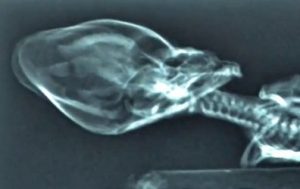

In afara de talia sa uimitor de mica, „Ata” are un cap foarte mare in raport cu corpul (asa cum sunt reprezentati adesea extraterestrii umanoizi in creatiile SF) si anumite particularitati cu totul neobisnuite ale scheletului trunchiului – de pilda, are doar 9 perechi de coaste, in loc de 12 cate exista in mod normal la om.

Scepticii au afirmat ca e vorba despre un fals, dar tomografiile arata ca este vorba despre un organism real. Alte ipoteze in spirit pozitivist au sugerat ca ar fi vorba despre o maimuta de mici dimensiuni sau de un fat avortat..

Insa investigatiile realizate cu mijloace performante – radiografii, tomografii, analize ADN – arata altceva, scotand la iveala informatii extrem de interesante despre umanoidul din Atacama: In primul rand, nu e vorba despre  o maimuta. „Pot spune cu certitudine absoluta ca nu este o maimuta. Este uman – este mai apropiat de om decat cimpanzeii”, a declarat Garry Nolan, directorul sectiei de biologie a celulelor stem de la Facultatatea de Medicina a prestigioasei Universitati Stanford din SUA, unde au fost realizate analizele genetice. Insa nu este vorba nici despre un fat avortat. „A trait pana la varsta de 6 sau 8 ani”, a declarat acelasi specialist. Cercetatorii au analizat ADN extras din maduva osoasa prezenta in coastele exemplarului, din care au obtinut,, după propriile declaratii, „material ADN de calitate excelenta”.

Concluzia specialistilor a fost ca era vorba despre „o mutatie interesanta” a unui individ uman de sex masculin, care a trait pana la varsta de 6 sau 8 ani.